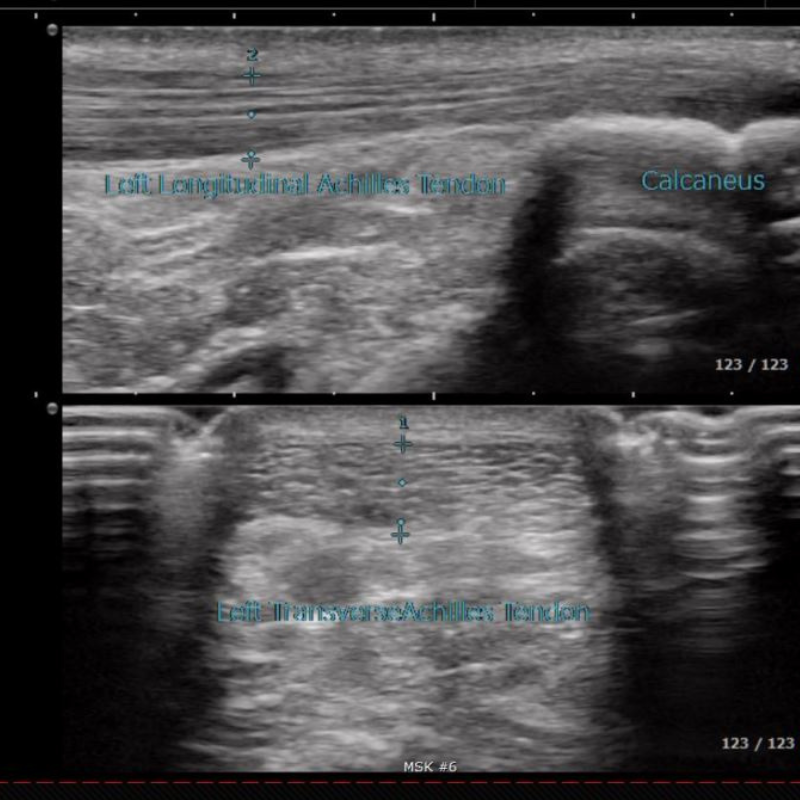

Diagnostic ultrasound works much like the device used during pregnancy to capture images of a baby in the womb. In podiatry, we use this safe, non-invasive tool to see tendons, ligaments, joints, and even bone in real time. Unlike X-rays or MRIs, ultrasound allows our podiatrists to gently move and stress your joints during the scan, giving a more complete understanding of what’s causing your pain.

Our podiatrists use diagnostic ultrasound to evaluate a wide range of conditions with precision and accuracy.

• Tendonities or Tendon injuries (Achilles, peroneal, posterior tibial)

• Cysts and bursitis

• Inflammatory conditions